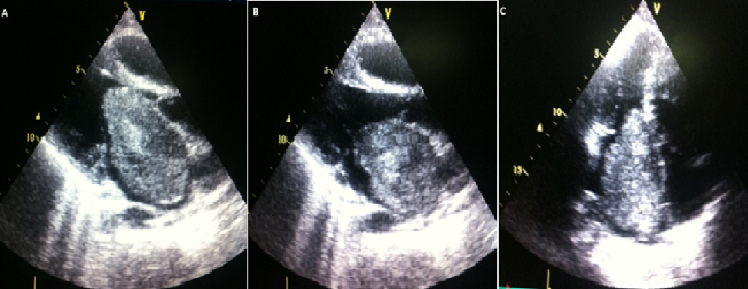

Myxome géant de l’oreillette gauche appendue à la valve mitrale

Le myxome cardiaque est la tumeur primitive intracardiaque la plus fréquente de l'adulte. Il est caractérisé par un polymorphisme clinique qui peut être déroutant pour le clinicien. L'avènement de l'échocardiographie en a bouleversé l'approche diagnostique. Malgré sa nature histologique bénigne, sa localisation intracardiaque engage le pronostic vital et impose une cure chirurgicale en urgence avec un risque de mortalité postopératoire minime. Le risque de récidive à long terme impose une résection large, une exploration minutieuse des quatre cavités et un suivi échocardiographique régulier. Nous rapportons le cas d'une jeune femme de 28 ans, sans aucun facteur de risque cardiovasculaire, reçue en consultation externe pour une dyspnée d'effort stade II de la NYHA évoluant depuis près de six mois. L'interrogatoire exclut une notion d'angines à répétitions dans l'enfance, de perte de connaissance et de déficit sensitivomoteur. L'examen physique révèle un roulement diastolique au foyer mitral. L'électrocardiogramme a montré un rythme sinusal, régulier à une fréquence cardiaque de 75 c/min avec une hypertrophie atriale gauche. Grâce à l'échocardiographie transthoracique, on a mis en évidence une masse insérée au niveau du septum interauriculaire occupant la totalité de l'oreillette gauche, hétérogène à surface irrégulière, appendue à la face atriale de la valve mitrale antérieure et traversant l'orifice mitral lors de la diastole et refoulée dans l'oreillette gauche pendant la systole. La patiente fut adressée directement à un service de chirurgie cardiovasculaire pour résection chirurgicale de la tumeur avec des suites simples.